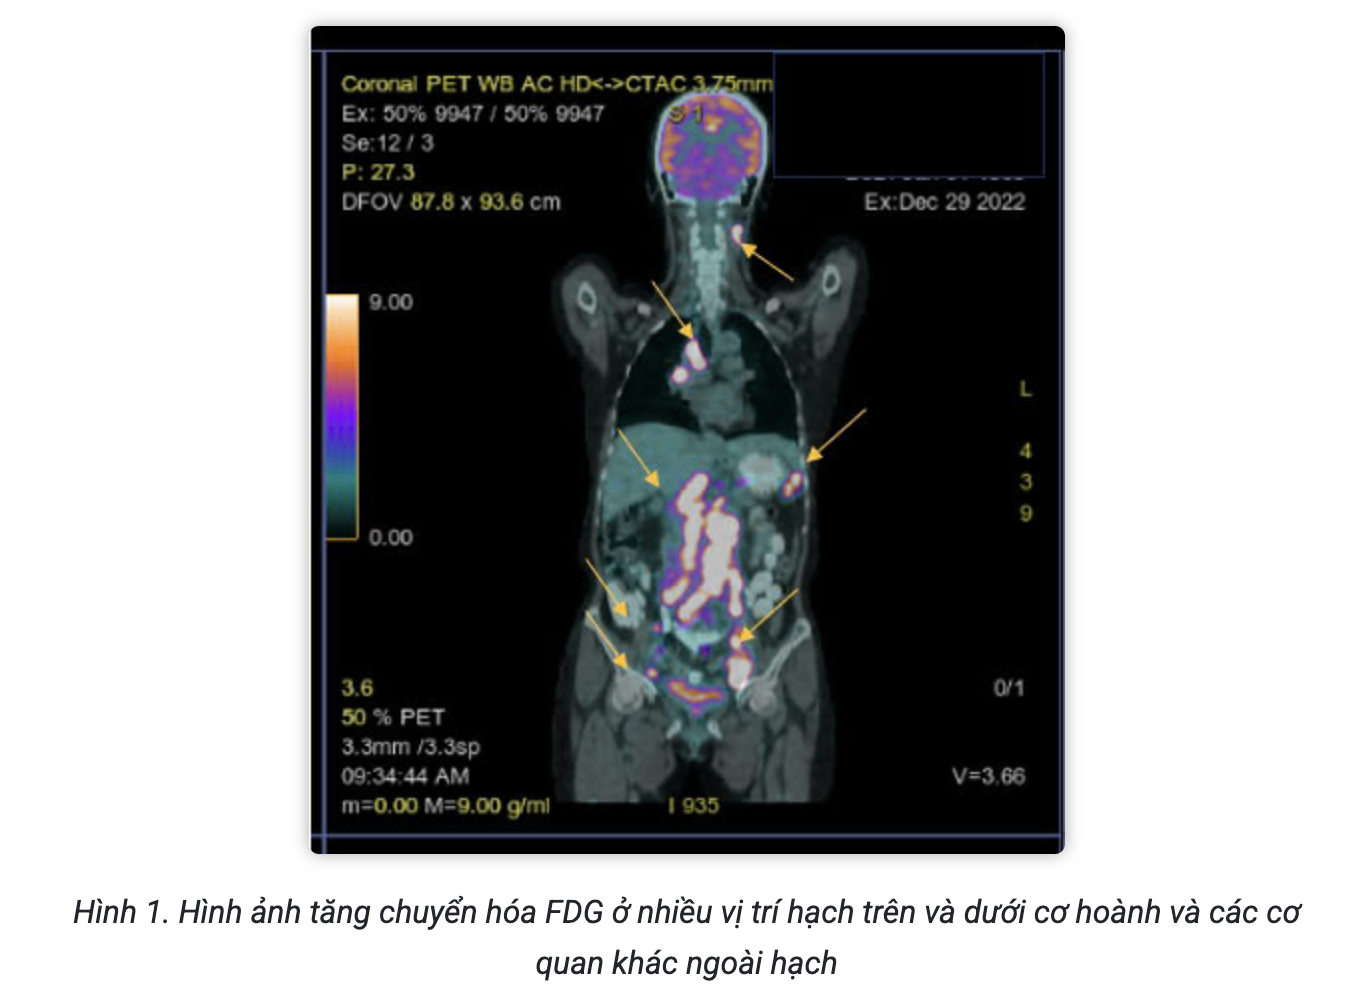

Hình ảnh PET/CT với F18-FDG đánh giá giai đoạn trước điều trị:

Kết luận:

- Hình ảnh hạch cổ 2 bên, hạch trung thất, hạch ổ bụng, hạch bẹn 2 bên tăng chuyển hóa FDG hướng tới ác tính.

- Hình ảnh nốt tổn thương phổi phải, tổn thương xương bướm, tăng chuyển hóa FDG hướng tới ác tính.